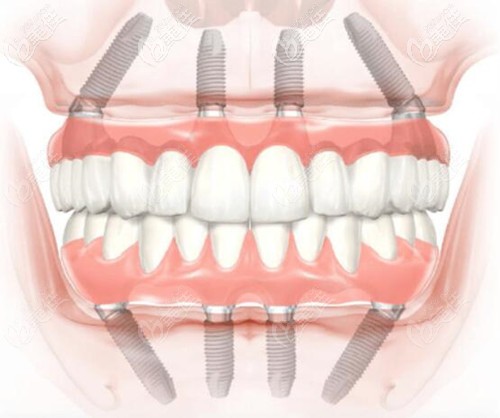

現(xiàn)在的全口種植牙無需28顆,基本上就是6-8顆就可以了,因此在選擇種植體材料上有了很多的空間,那要是選擇諾貝爾PCC種植牙一顆多少錢呢?

滿口種植牙大概多少錢,5萬塊錢能種植全口牙嗎?現(xiàn)在牙齒缺失的朋友越來越多,主要糾結(jié)的就是六十歲老人種牙好還是鑲牙好?今天小編就一一給大家解釋下你所關(guān)心的事情。

牙齒活動需要拔掉做種植牙修復(fù)嗎?很多人多小都有些牙齒晃動,如果晃動的厲害確實需要拔掉做種植牙,那么韓國美格真全口種植怎么樣?